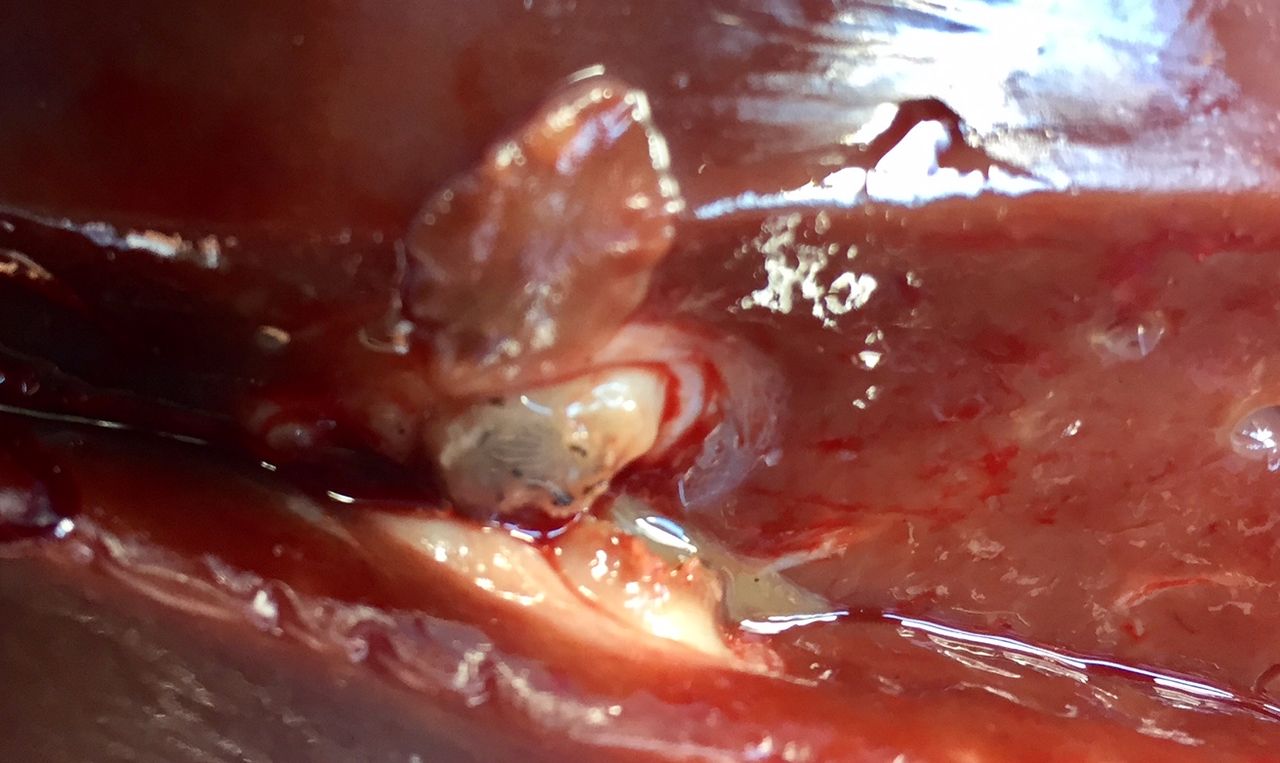

Farmers focus on having an animal’s diet nutritionally balanced to achieve high performance; yet if they neglect the treatment of liver fluke – they are essentially feeding concentrates to an animal with potentially severe liver damage and therefore have reduced performance.

Albendazoles, Clorsulon and Oxyclozanide products will only target mature fluke (10-12 weeks old), this being fluke which have left the liver and reached the bile duct.